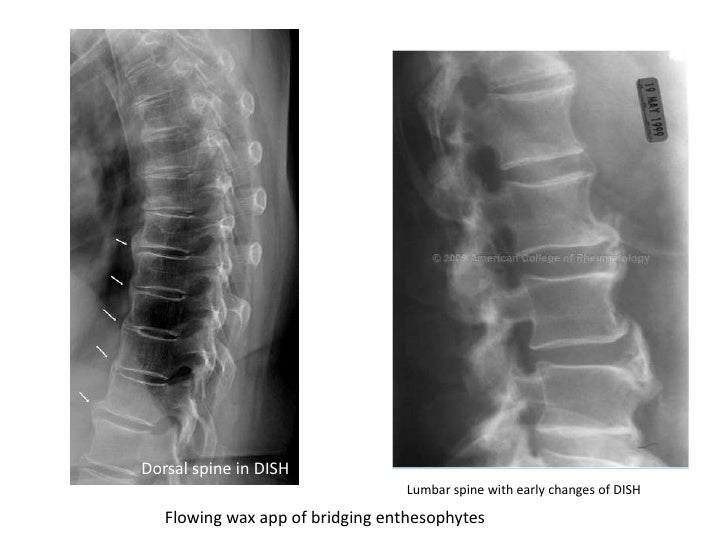

Even low energy trauma could lead to a serious fracture. So someone with the condition suffers a fall and lands on their back has an increased risk of a fracture. A healthy spine is flexible enough to distribute the force from a fall or hit and prevent injury. It is usually asymptomatic/without symptoms or mildly symptomatic. Diffuse Idiopathic Skeletal Hyperostosis Symptomsĭiffuse Idiopathic Skeletal Hyperostosis SymptomsĪn important reason that diffuse idiopathic skeletal hyperostosis is not recognized and underdiagnosed is that many individuals do not experience symptoms.